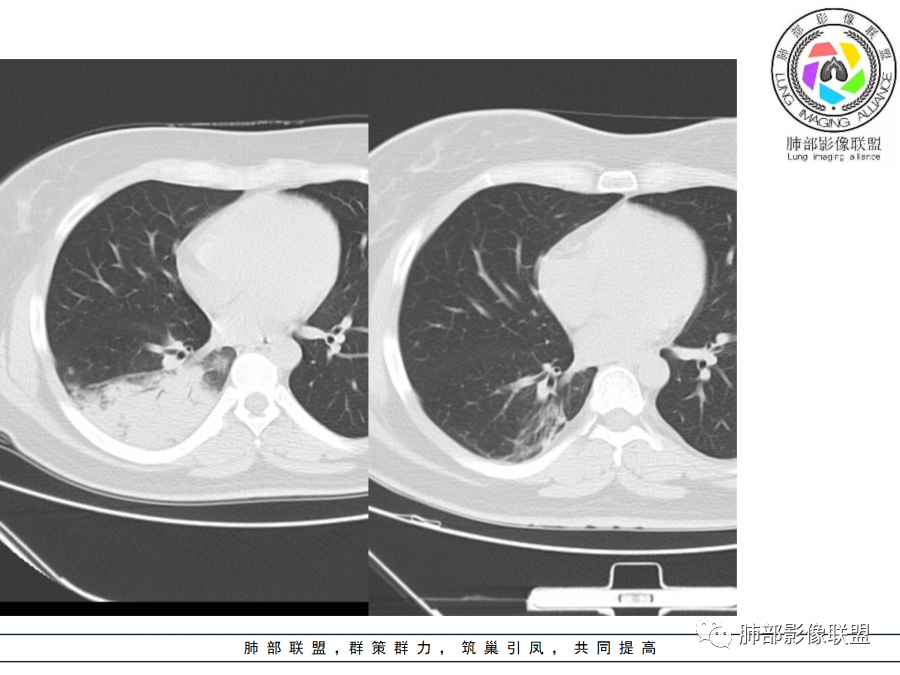

细菌性肺炎是沿着支气管往周围肺泡散开,内朝外,沿着叶段分布,受到支气管管辖,呈扇形,与支气管长轴平行,与胸膜垂直,隐球菌就是外朝内,外就是肺小叶内的肺泡,外周的。

肺小叶。他就是一个个肺小叶的融合,胸膜平行,和病毒一样。只是病毒在间质,是肺小叶分布的毛玻璃。隐球菌是肺实质,肺泡,肺小叶的实变。

这个病变换个角度看

这个病例呢?没有。如若考虑细菌性的,那还是应该是大叶性的,靠近大支气管蔓延的。小叶性融合的,也还是有细支气管的一些特点出来。

病毒呢,有个特征意义的-细网格征。磨玻璃区域的病变内是沿间质蔓延为主的特点。

这个病例周围磨玻璃病变仅有几个小叶间质增厚,没有细网格征,还是肺实质病变为主,小叶内间质增厚不明显,从分布特点就不符合。

这个病变也不是一个起源中心,胸膜下,多发结节状、实变影。而大叶性肺炎多数由内-外大片状。所以是肺实质多发融合病变。单纯从影像上,还是比较符合隐球菌特点,胸膜下,多发、多中心,相互融合(兄弟齐心)。

我感觉大叶性肺炎是偏高位的中心一点的内向外。病毒是外向内的间质(肺小叶层面),隐球菌这种是外向内实质(位置偏外偏下的肺泡,多灶的融合)

你看实性部分,有很多小结节的实性部分,分布很散,不是一个区域,不是按一个段过来的,是多个段,但是内基底段似乎又不受累。所以大叶性肺炎,一般细菌性的这个影像特点还是不太支持。